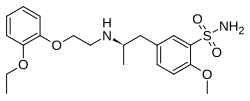

| Tamsulosin | Flomax |

|

A blocker that has slight selectivity for α1 receptors.[2] | Relaxation of prostatic smooth muscle.[2] |

| |